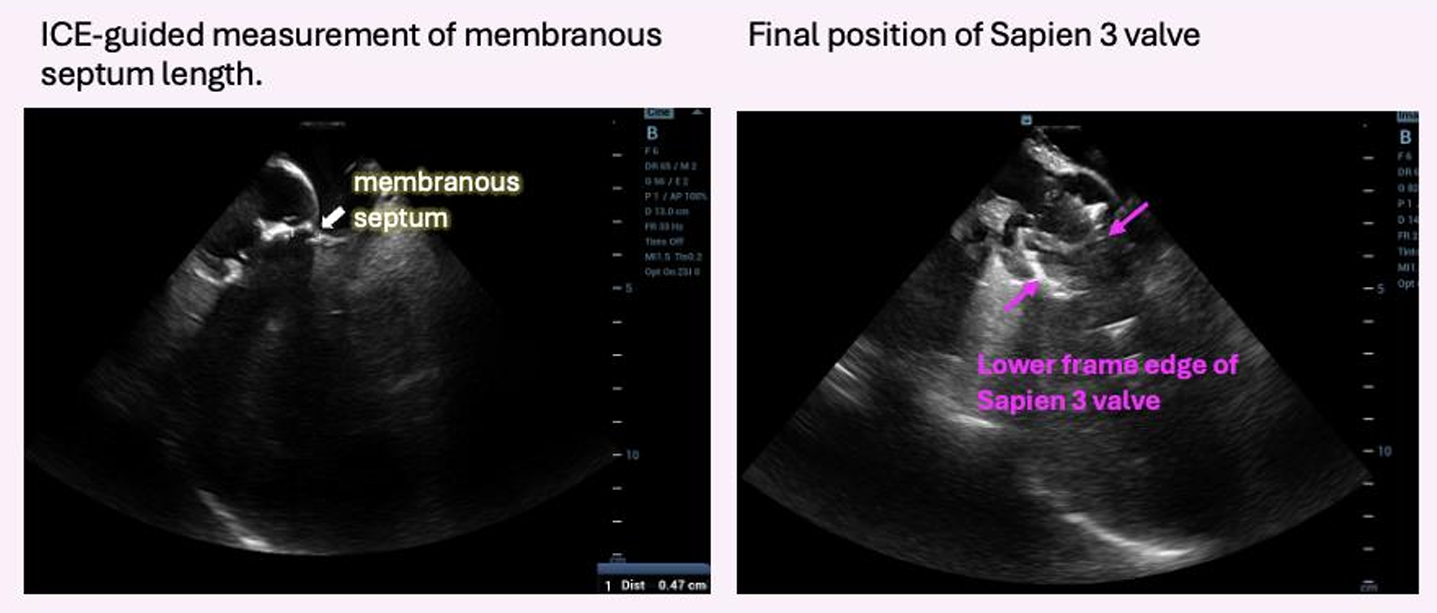

Pre-procedural electrocardiography showed a bifascicular block. Given the high surgical risk and concern for conduction disturbance, a 26-mm short-frame Sapien 3 valve was selected. Intracardiac echocardiography was used for real-time monitoring of valve position and anatomic relationships during implantation. The mean aortic valve pressure gradient measured by catheterization was 35.5 mmHg before valve deployment.

Under general anesthesia, arterial and venous access were obtained via the right femoral artery and vein. A temporary pacing lead was inserted for rapid pacing; however, consistent capture could not be achieved under fluoroscopic guidance. Therefore, intracardiac echocardiography (ICE) was advanced into the right heart to allow precise, close-range localization of the pacing lead. ICE was continuously used to provide real-time monitoring of valve positioning, implantation depth, and the spatial relationship between the transcatheter valve and the membranous septum. A 26-mm Sapien 3 valve was successfully deployed under temporary pacing. Post-deployment angiography and ICE confirmed optimal valve position without conduction disturbance, paravalvular leak, or other complications. The mean aortic valve pressure gradient decreased from 35.5 to 11.2 mmHg. The patient recovered uneventfully after the procedure.

Bifascicular block is a strong predictor of permanent pacemaker implantation after transcatheter aortic valve implantation. Because the conduction system runs through the membranous septum, real-time intracardiac echocardiography (ICE) guidance enables precise depth control and may reduce the risk of new conduction block. In this case, ICE allowed accurate localization of the temporary pacing lead and continuous monitoring of valve positioning during transcatheter heart valve deployment. Postoperative electrocardiography showed no new conduction abnormalities, supporting the role of ICE in improving procedural precision and safety in high-risk patients.